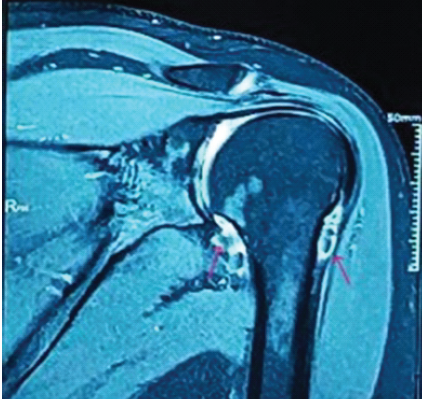

Understanding Synovial Chondromatosis: A Rare Cause of Shoulder Impingement

Ashish Kumar , L Purushotham

………………………………p.162-166